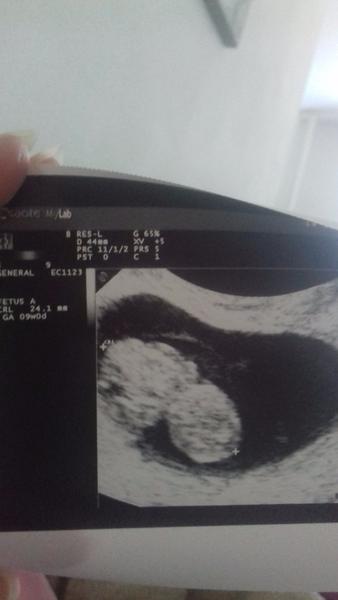

Baby mojeee aha ďalší😁 neverím vlastným očiam 🙈 o 2hodky výsledky krvi.